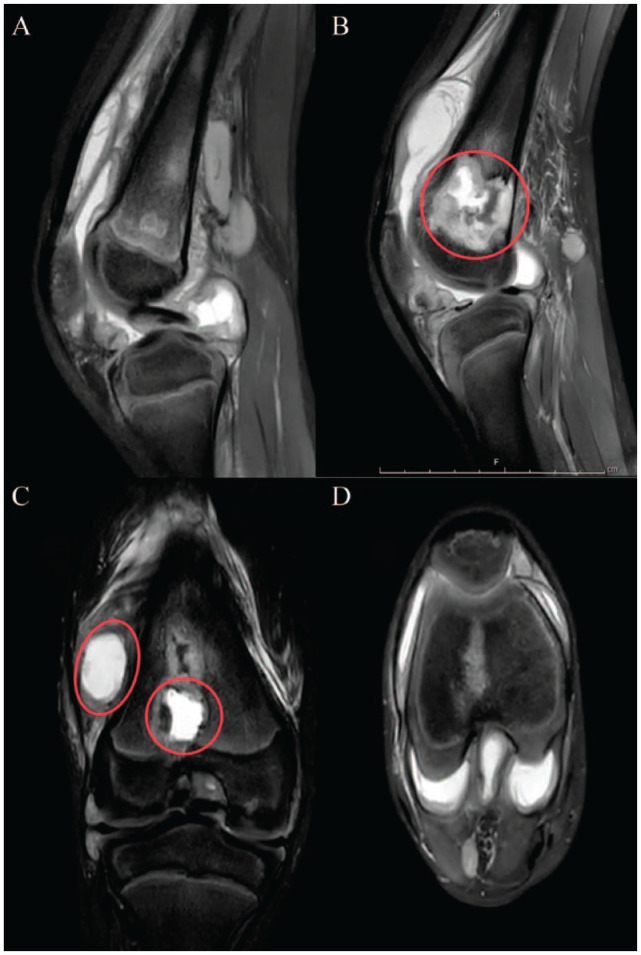

Case presentation: We report a rare case of a 9-year-old male diagnosed with right knee tuberculosis after enduring severe symptoms for several months. Despite multiple negative biopsies and aspirates during initial debridement surgeries, a biopsy taken 6 months later confirmed the presence of Mycobacterium tuberculosis (MTB). The patient was subsequently treated with debridement and anti-tubercular therapy.

Conclusion: This case underscores the critical need to consider tuberculosis in patients presenting with chronic bone pain to avoid misdiagnosis, particularly in the developing world. The atypical presentation of osteoarticular tuberculosis in this young patient emphasizes the need for healthcare professionals to recognize subtle symptoms. Advanced imaging studies like MRI and microbiological evaluations, including site biopsies, are essential for accurate diagnosis. Increased awareness and collaborative research are crucial to improving the understanding and management of pediatric osteoarticular tuberculosis and extrapulmonary tuberculosis.